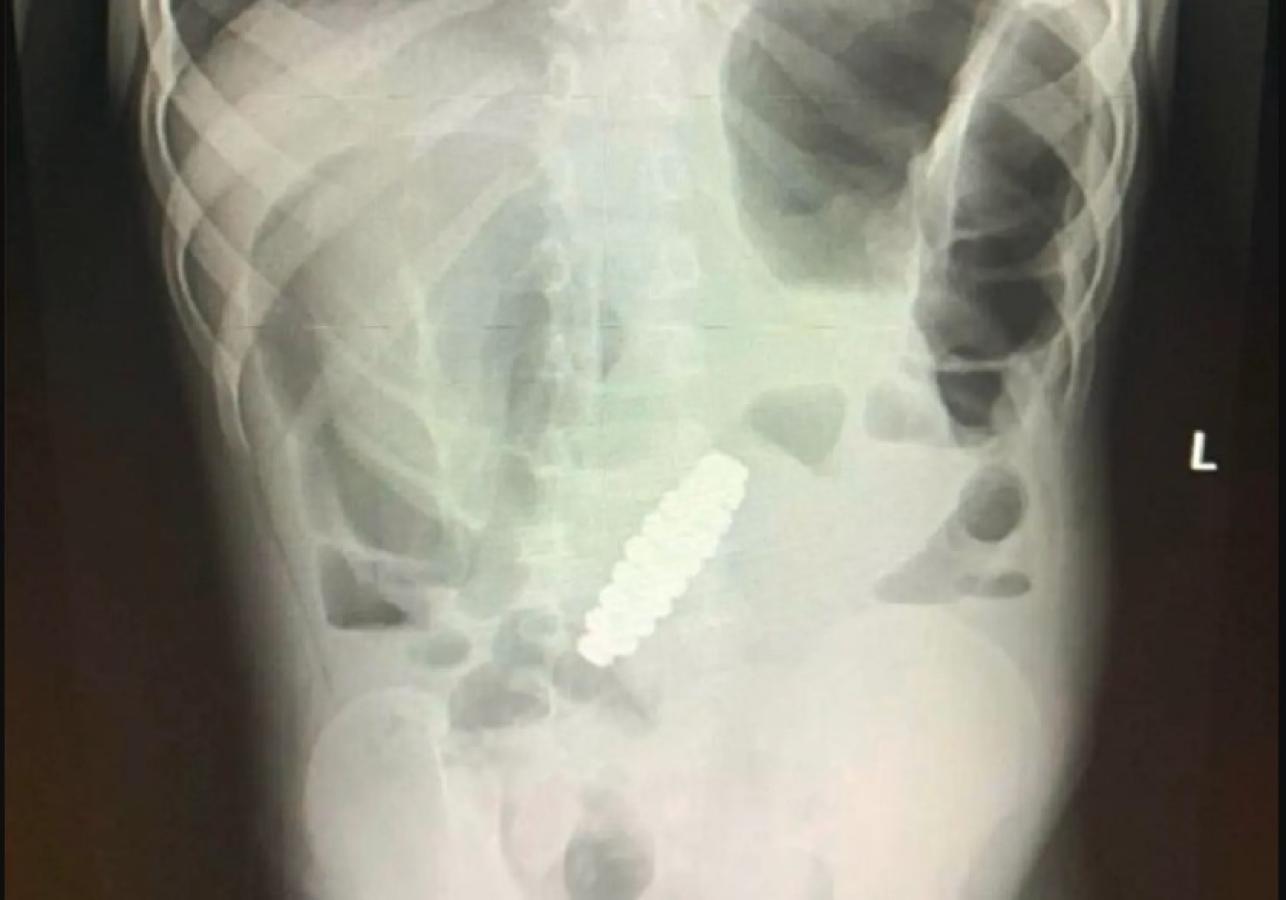

En la ecografía se mostraba que el niño tenía un extraño objeto en sus intestinos. Debido a esto, los médicos le realizaron una laparotomía urgente para sacarlo.

Finalmente, lograron sacar de forma exitosa el objeto, que resultó ser una pulsera hecha de 18 cuencas magnéticas de forma hexagonal. El brazalete obstruía los intestinos y los estuvo presionando, formando cuatro pequeños agujeros en ellos.